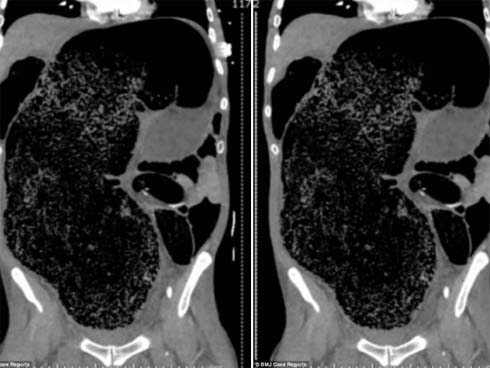

Qua thăm khám và kết quả chụp phim, bác sĩ chẩn đoán bé bị hội chứng phình đại tràng bẩm sinh, khiến một đoạn đại tràng không có dây thần kinh để kiểm soát sự co bóp đại tràng và được chỉ định phẫu thuật gấp.

Trong ca mổ kéo dài 3 giờ, ê-kíp bác sĩ đã cắt bỏ phần trực tràng bị phình dài gần 20 cm, dãn to 20 cm, cùng gần 3 kg phân ứ đọng bên trong, dù đã được thụt tháo bơm rửa trước phẫu thuật.